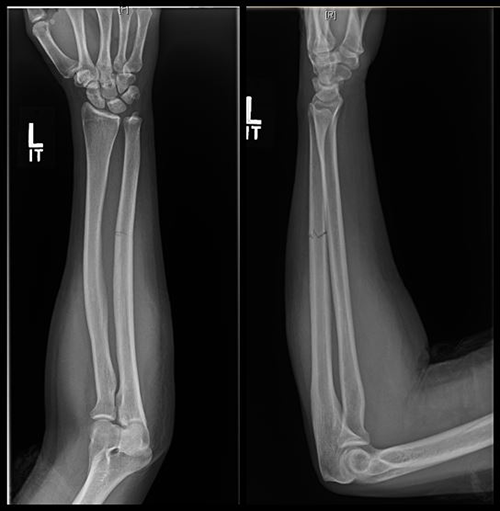

Review of reports by two experienced emergency radiologists revealed that both intimate partner violence and suicidal behavior played independent roles in doubling the overall injury rate compared to that of patients without a history of intimate partner violence or suicidal behavior. Patients with intimate partner violence often sustained head, face, neck and upper limb injuries—areas commonly hurt during assaults.

Intimate partner violence patients with suicidal behavior suffered over six times as many head/face/neck injuries, almost four times as many spinal fractures, three times as many deep injuries, and twice as many upper extremity injuries. These patients experienced almost twice as many severe injuries and three times as many mild injuries.

When looking at independent effects of intimate partner violence versus suicidal behavior, the researchers found that suicidal behavior had a greater impact on the injury rate of upper extremity injuries, while intimate partner violence had a greater impact on head/face/neck injuries.

Figure 1. Intimate Partner violence fracture to ulna bone.